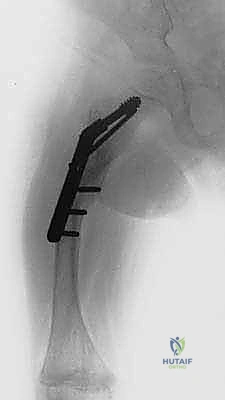

الخطوة الرابعة: إدخال المسمار التلسكوبي

بعد تقويم العظم وجعله مستقيماً كحبات المسبحة على خيط، يتم إدخال السلك الدليلي (Guide Wire). ثم يتم إدخال الجزء الخارجي (الأنثوي) من المسمار التلسكوبي وتثبيته في الجزء العلوي من العظم (Epiphysis).

بعد ذلك، يتم إدخال الجزء الداخلي (الذكري) من المسمار عبر الجزء السفلي من العظم وتثبيته في المشاشة السفلية. هذا التصميم العبقري يضمن حماية العظم بالكامل من الداخل.

تُعد هذه العملية من أدق العمليات في جراحة عظام الأطفال، وتتطلب مهارة استثنائية كما هو الحال مع البروفيسور محمد هطيف. يتكون المسمار التلسكوبي (Fassier-Duval) من جزأين يتداخلان ببعضهما البعض (مثل التلسكوب). يتم تثبيت أحد الأطراف في أعلى العظم والطرف الآخر في أسفله. عندما ينمو العظم، ينزلق الجزء الداخلي من المسمار للخارج، مما يسمح للعظم بالنمو الطبيعي دون أن ينثني أو ينكسر.